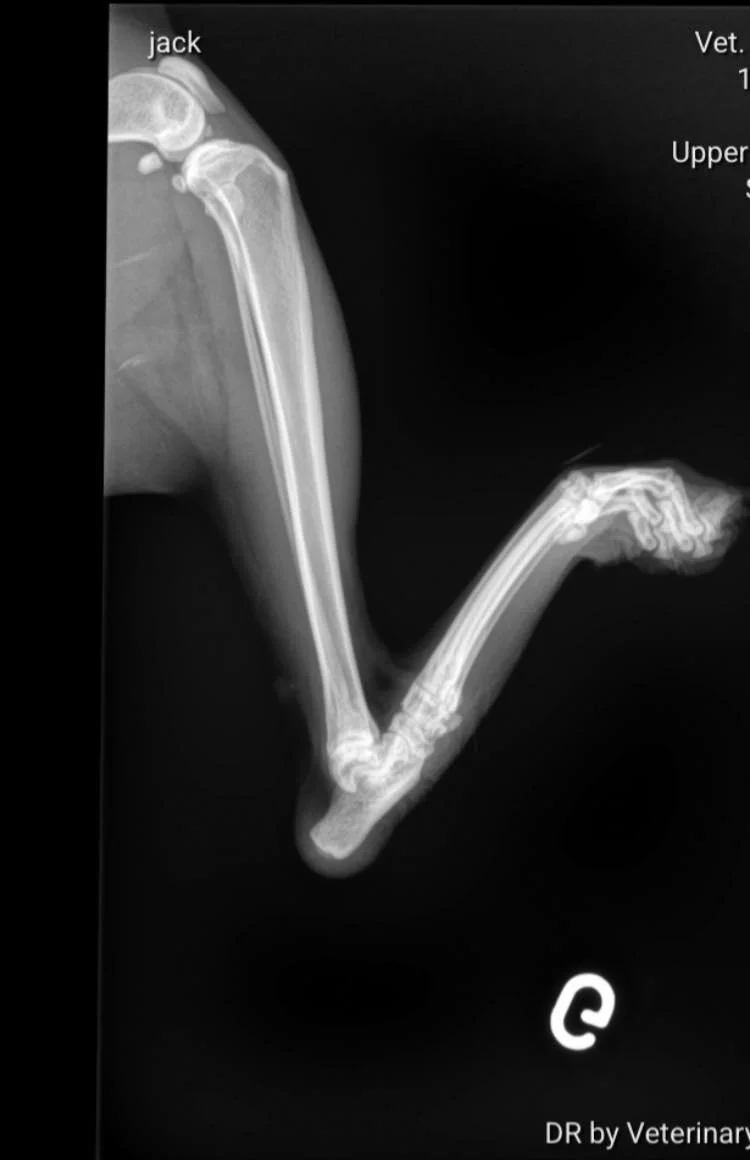

Une arthrodèse a été réalisée sur une de ses pattes afin de bloquer l articulation et empêcher le frottement constant avec le sol.

Cette opération nous a coûtée 1.500€ pour une seule patte, s’ajoutent à cela les soins et radios qui ont déjà été réalisées auparavant. Nous sommes à plus de 2.500€ de frais vétérinaires pour lui à ce jour.